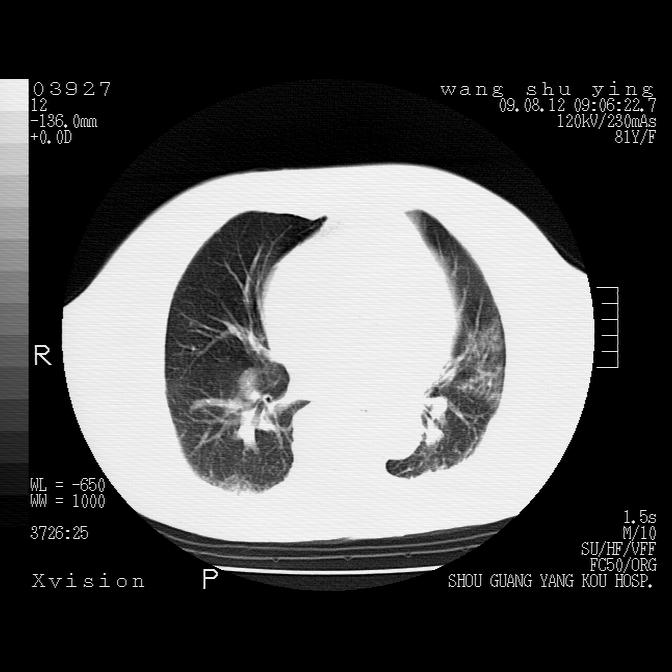

以下是引用帅河马在2009-8-12 12:59:00的发言:[br]两肺感染性病变伴双侧胸膜肥厚。[br]左侧甲状腺腺瘤不除外。[br]腹水+心包积液。[br][br][本贴已被 帅河马 于 2009-8-12 13:14:32 修改过]

以下是引用sdzyy在2009-8-12 18:17:00的发言:[br]两肺感染性病变伴双侧胸膜肥厚。[br]左侧甲状腺腺瘤不除外。[br]腹水+心包积液。[br]支持

以下是引用随光逐影在2009-8-12 19:42:00的发言:[br]1)两肺感染性病变伴双侧胸膜肥厚。2)不排除左侧甲状腺腺瘤。3)肝脏占位性病变;建议行进一步检查。